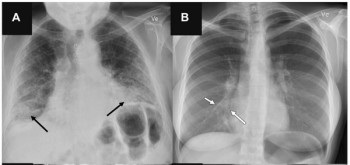

In a multicenter study examining four commercially available artificial intelligence (AI) software products for chest X-rays in over 2,000 patients, researchers found sensitivity rates ranging between 33 to 61 percent for vague airspace disease and 9 to 94 percent for small pneumothorax and pleural effusion.